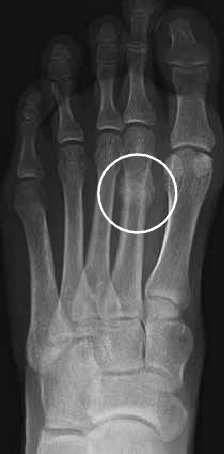

Bien que non spécifique à cette condition, habituellement la douleur au pied apparaît graduellement, augmente en mettant du poids sur le pied et en courant et diminue avec le repos. En progressant, la douleur provoquée par la fracture de stress devient sévère et survient durant les activités quotidiennes normales. Il y a parfois une enflure et/ou une ecchymose au-dessus du pied. La région de la fracture est sensible à la palpation. La radiographie est souvent utilisée pour confirmer le diagnostic, mais il est à noter que la fracture de stress n’est visible avec les rayons-x qu’après un certain temps.